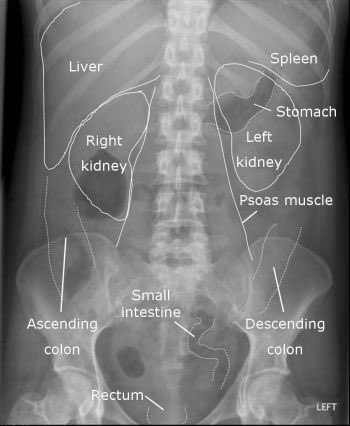

📍قبل لا نبدأ، لازم نتعرف على شكل الأشعة الطبيعية للبطن 👇🏻🌟

Abdominal XR